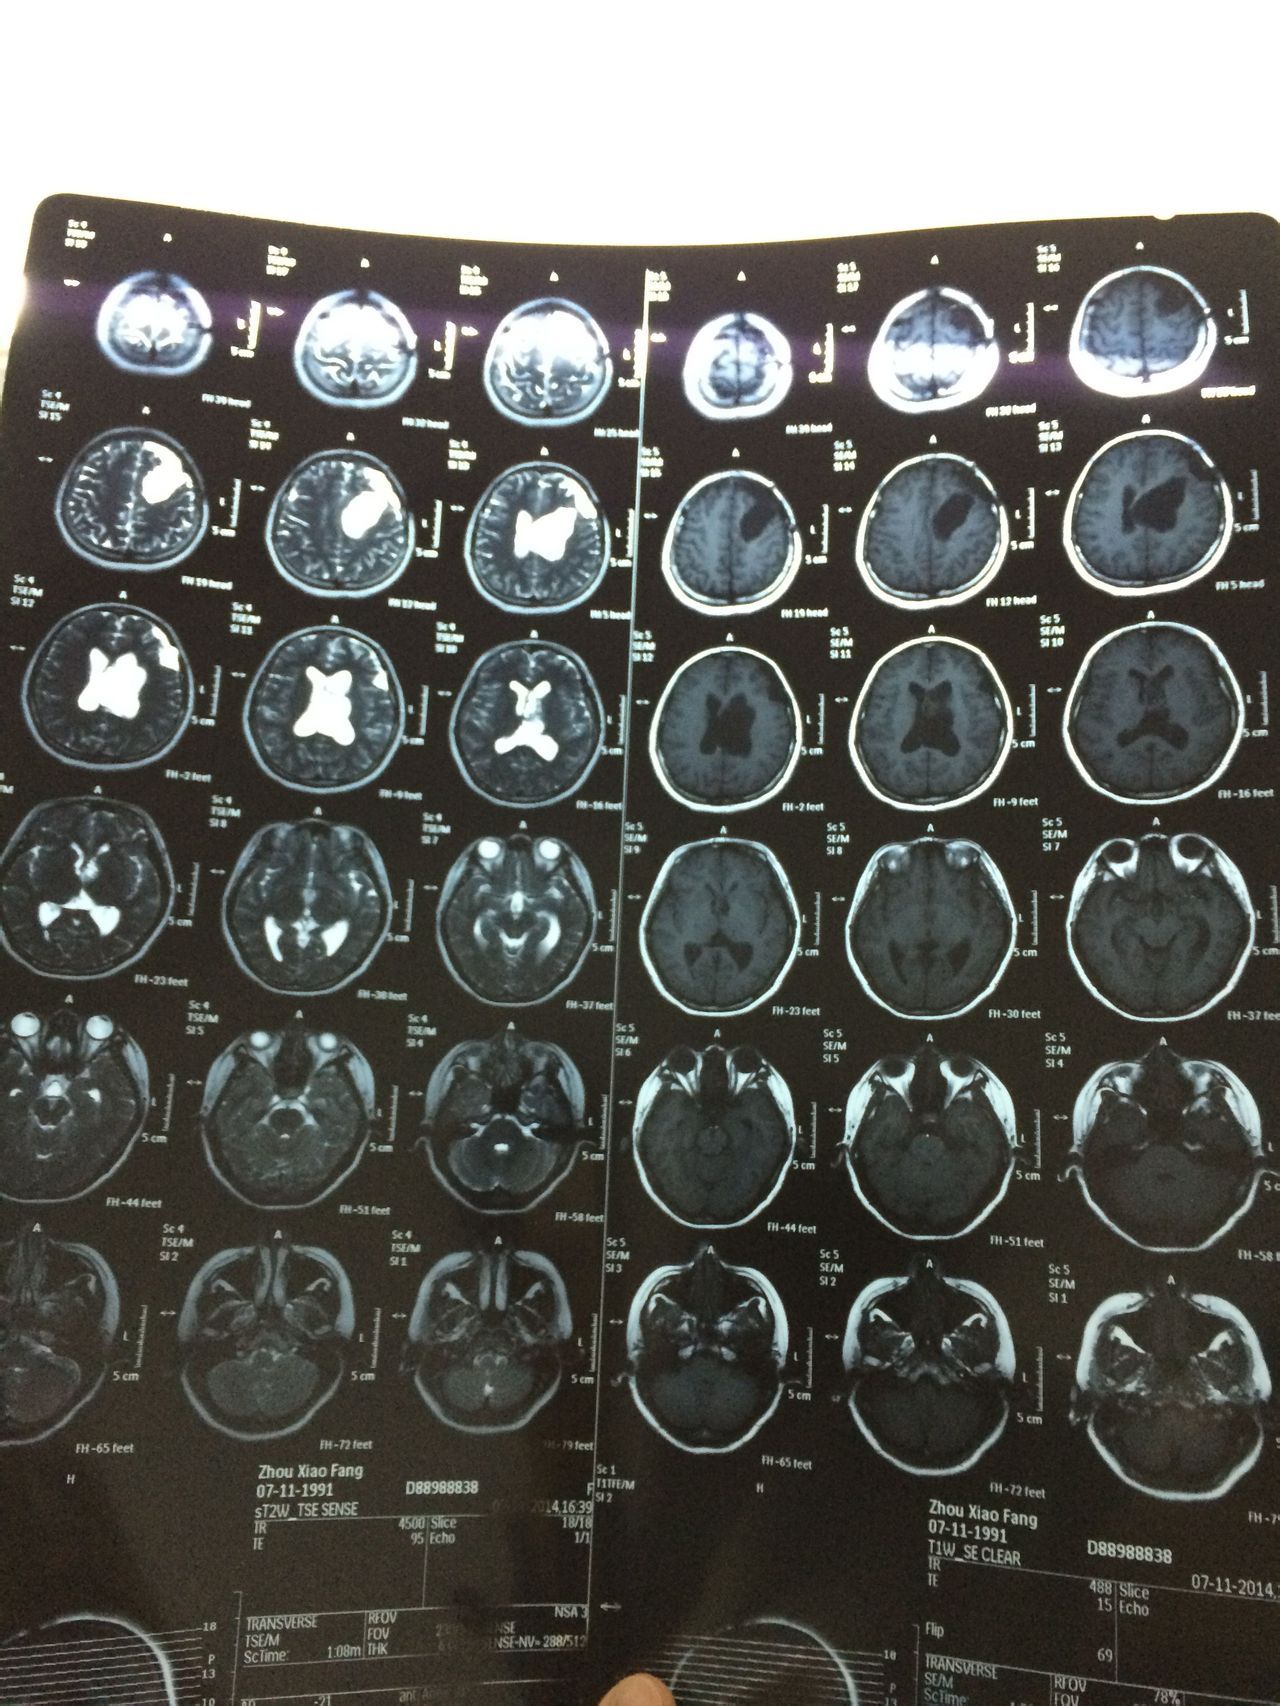

患者女,23岁。2011年9月脑胶质母细胞瘤外科手术,术后无措施,半年复查核磁共振。2013年5月做伽马刀治疗。持续每半年复查核磁共振。    患者身体状况良好,生活上基本没有问题。偶尔出现头晕不排除感冒等因素,但是如果晃到脑部,会有头晕或疼痛感出现。    另外,患者在手术前,经期不规则,大体上一两个月一次,时间不确定。术后,经期不规则更严重,2-3月一次,时间也不固定,但是量少,时有淤血,做过性激素水平检查及妇科常规,正常。2014年11月复查报告麻烦查看附件。    疑问:    1、患者现在需要积极的治疗吗?    2、患者的脑积水严重吗?在这三年内,脑积水虽有波动(增减),但是大体上在一个程度,较稳定。需要做颅内压检查吗?    3、患者现在适合备孕吗?(一直在避孕,暂时未知是否影响怀孕。)这个问题比较复查,还希望各位专家能给予分析利弊。(谢谢!)    3.1、怀孕各个阶段对患者的肿瘤是促进还是抑制作用是否有临床经验供参考?是否可以做一下评估。    3.2、怀孕各个阶段是否会患者造成负担,使其脑积水等加重?    3.3、如果现期不适合备孕的话,有存在“等待”的必要?也或许以后也是这种情况?    最后,很感谢各位专家百忙之中能够为本人了解这份信息。本人是患者的丈夫,发这个问题上来,只是想了解一下情况。虽然我们都很希望能够有爱的结晶,但是我十万分不愿意我的爱人去冒险。各位专家,希望能给予详细的说明和建议。    衷心的祝福你们。

根据影像可以看到脑室轻度扩大,脑胶导劣报质母细胞瘤恶性程度非常高,且术后复发率很高,乔实再加上已经做了伽马刀,对垂体功能影响无法判断。目前治疗口服替莫唑胺治疗,是否可以怀孕,还们院是建议咨询产科医师,详细的检测体内激素水平。